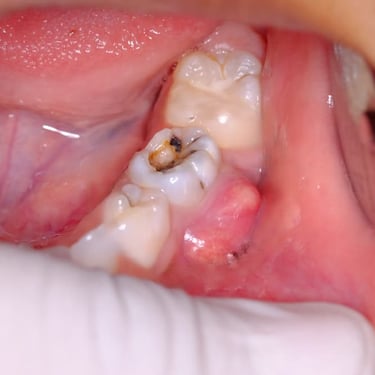

Pulpitis Crónica Hiperplásica

La pulpitis crónica hiperplásica es una inflamación de la pulpa con crecimiento excesivo de tejido pulpar a través de una caries abierta.

Los pacientes notan un tejido rojo que sobresale de la cavidad dental.

El tratamiento incluye la eliminación del tejido afectado y un tratamiento de conducto. Es crucial tratar la caries para evitar infecciones adicionales.